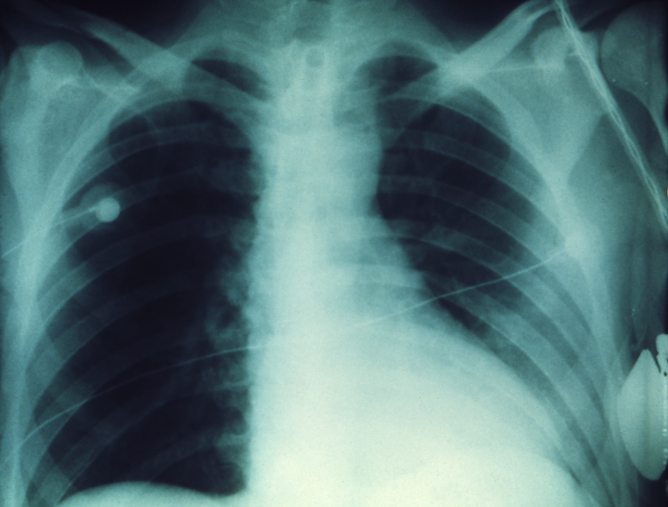

感染鼠疫后的肺部。病人未经治疗,一周内死亡。(图片来源:CDC/ Dr Jack Poland, CCBY)